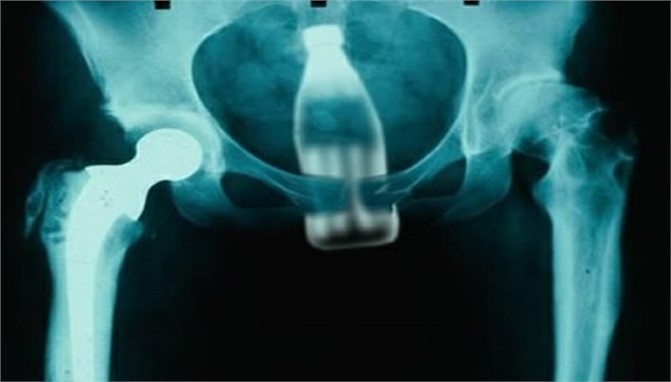

Tarsusta 45 yaşında adam gece saatlerinde makatına şişe kaçma vakası meydana geldi. Gece geç saatlerde Tarsus Devlet Hastanesi Aciline geldi.

Burada yapılan incelemede şişenin içerde oldukça ilerlediği ve operasyonla çıkarılabileceği anlaşıldı. Operasyona alınan A.Ö., yapılan operasyonla şişeden kurtuldu.Hastane yetkililerinin olayı emniyet güçlerine bildirmesi sonrasında yapılan araştırmada A.Ö’nün ifadesinde şişenin kaşırken kaçtığını beyan ettiği öğrenildi.